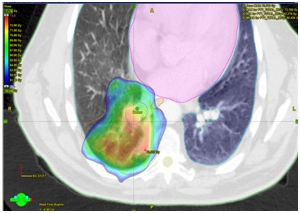

Рекомендована химиолучевая терапия: на основной процесс в правом легком, лимфоузлы средостения до СОД 66Гр за 33 фракции на фоне еженедельного введения химиотерапии: Паклитаксел 50 мг/м2 + Карбоплатин 2 AUC.

18.01.2017 – 03.03.2017. Радикальный курс лучевой терапии на первичный очаг в правом легком и зоны регионарного лимфоотока (ПЭТ – позитивные лимфоузлы средостения) в разовой дозе 2Гр до суммарной дозы 66 Гр за 33 фракции. Продолжительность лечения 6 недель. Выполнено 6 введений Паклитаксел 50 мг/м2 + Карбоплатин 2 AUC еженедельно.